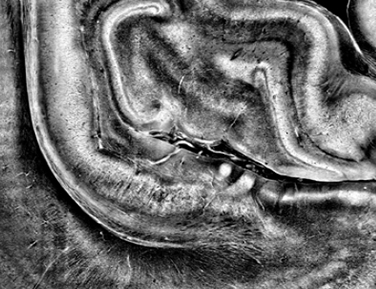

black_white_brain